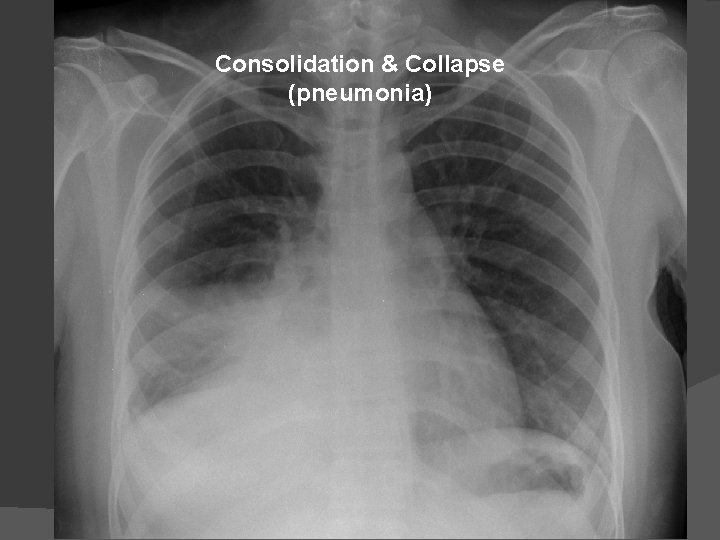

Consolidation & Collapse (pneumonia)